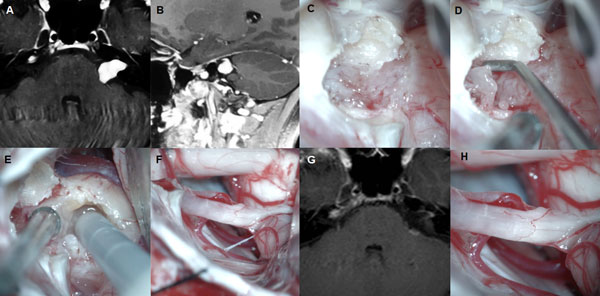

Figura 2: Paciente masculino de 59 años, operado de SV T1 izquierdo. A-C: RM preoperatoria. D-I: hallazgos intraoperatorios. J-L: RM postoperatoria.